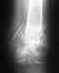

Вывих эндопротеза?

мне 47 лет.17 февраля 2012 года перенесла операцию по эндопротезированию тазобедренного сустава. Все шло нормально,но 2 дня назад я упала на пол, на спину. Я в шоке. болит нога,но терпимо, нет отеков,синяков.Я ужасно испугалась и практически не встаю с постели.Ходить могу,движения не ограничены,но боюсь. Мужу не говорю,расстроится. Я знаю,что надо делать контрольный снимок.Хочу спросить, если был вывих или подвывих, то смогла ли бы я ходить, или какие жалобы у меня должны быть в случае какой либо опасности . Что бы посоветовали? Я ужасно нервничаю. Заранее благодарю!